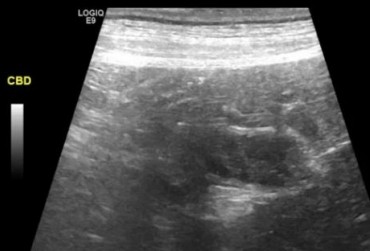

W artykule opisano przypadek dirofilariozy u psa wywołanej D. immitis. U badanego pacjenta stwierdzono patognomiczny obraz zmian w badaniu rentgenowskim i ultrasonograficznym układu sercowo-naczyniowego.